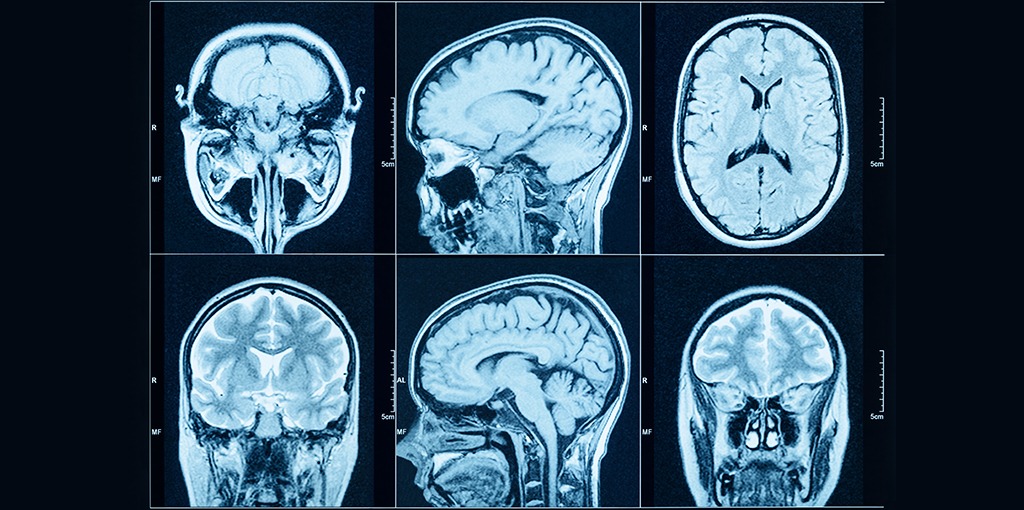

Every year, more than 300 cases of Glioblastoma, the most frequent and lethal brain tumor type, are being discovered in Sweden. Unfortunately, most patients die within a year from the diagnosis despite extensive surgery, radiotherapy and chemotherapy, and so far, the large amount of collected genetic data has not led to any major breakthroughs.